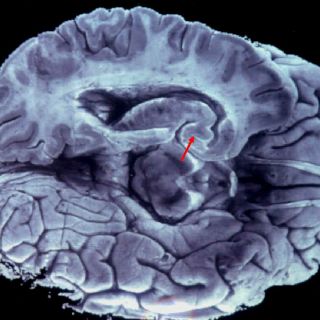

- Utilizamos sólo el 10 por ciento de nuestro cerebro. Esta teoría que se le ha atribuido infundadamente a Albert Einstein, es uno de los mitos más antiguos sobre nuestro cuerpo. De acuerdo al British Medical Journal (BMJ), investigadores han aclarado que la mentira surgió en 1907, para argumentar el potencial de las personas de desarrollar múltiples talentos. La verdad es que utilizamos el 100 por ciento de nuestro cerebro. Especialistas señalan que las imágenes de resonancia magnética y estudios del metabolismo cerebral, demuestran que durante el día no queda ninguna parte del cerebro sin ser activada. Lo importante es fomentar la actividad cognitiva y cerebral desde la infancia, porque eso mantiene y aumenta las conexiones cerebrales.

-La personalidad se define por el lado del cerebro dominante. Nada es más falso que decir que una persona es más creativa o más analítica porque utiliza más determinado lado del cerebro. La masa cerebral, sí tiene algunas estructuras especializadas que se encargan de realizar determinadas funciones, pero no se agrupan en un lado específico. Los científicos afirman que para ser verdaderamente creativos o analíticos, es necesario tomar recursos de ambos lados del cerebro.

Por otro lado, personas que han tenido que someterse a una cirugía donde se les extrae un hemisferio completo del cerebro, no pierden del todo su lado creativo o lógico. Incluso por lo general, recuperan una buena parte de las funciones que supuestamente corresponden a la parte extraída.